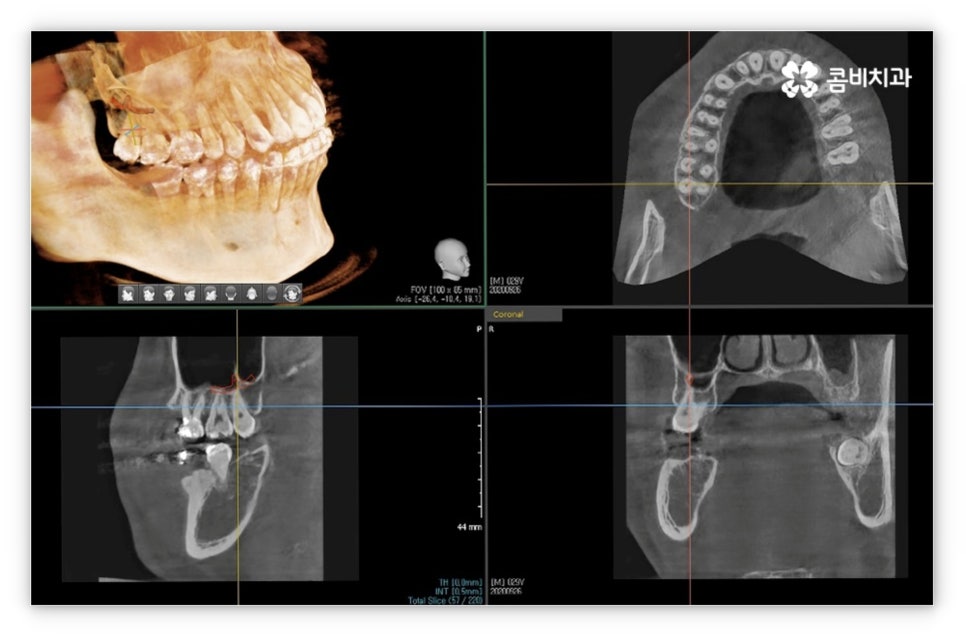

그리고 교정 치료는 그 목적상 위아래 교합이 똑바로 맞아 저작 기능을 제대로 수행할 수 있도록 하면서 가지런한 치열을 통해 발란스를 잡아주고 심미적으로도 좀 더 보기 좋은 안모를 형성하도록 하는 과정이기 때문에 환자의 치열과 교합, 얼굴 형태, 턱 관절 및 골격 구조 등 모든 부분을 세밀하게 파악하고 종합적으로 고려하여 각자에게 딱 맞는 교정 플랜을 세울 수 있도록 3D CT 와 같은 정밀 검진 기계를 갖추고 있는 치과에서 치료 받으시길 권유드리고 있는데요. 3D CT 는 일반 CT와 다르게 다각도에서 촬영을 하므로 환자분의 치아 위치, 턱관절, 얼굴의 정면 및 측면 등 다양한 정보를 수집하여 의료진 분들의 세밀한 파악을 돕는다는 장점이 있어요.